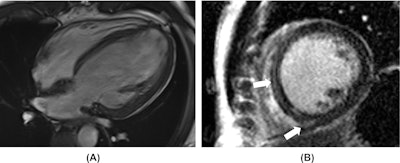

Amphetamine-associated cardiomyopathy. A 42-year-old man with a known history of amphetamine consumption presented with heart failure symptoms. (A) Cardiac MR four-chambers SSFP image in an end-diastolic phase reveals a severely dilated left ventricle. Functional analysis showed a severely decreased left ventricular ejection fraction. (B) Short-axis late gadolinium enhancement slice depicts faint septal mid-wall and lower insertion point fibrosis (white arrows).